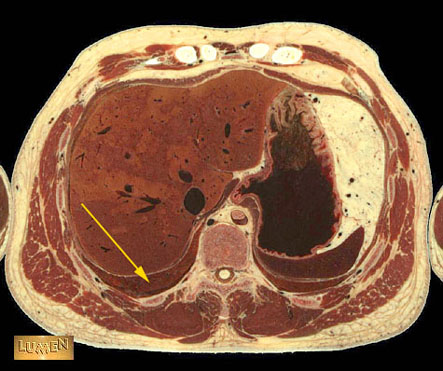

Question: Identify.

Answer

Lower lobe of right lung.